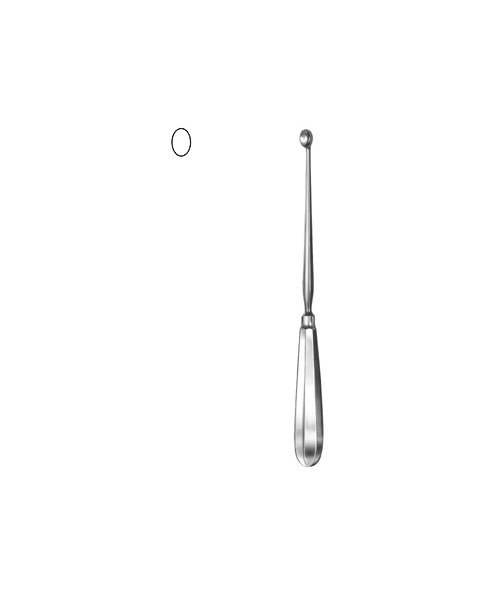

- Otology, Surgical Instruments

Ear Curette

- Size : 13 CM - 5"

- Read more

-

- Otology, Surgical Instruments

Ear Curette

- Size : 15 CM - 6"

- Read more

-

- Otology, Surgical Instruments

Ear Curette

- Size : 15 CM - 6"

- Read more

-

- Otology, Surgical Instruments

Ear Curette

- Size : 17 CM - 6 3/4"

- Read more

-

- Otology, Surgical Instruments

Ear Curette

- Size : 17 CM - 6 3/4"

- Read more

-

- Otology, Surgical Instruments

Ear Curette

- Size : 17 CM - 6 3/4"

- Read more

-

- Otology, Surgical Instruments

Ear Curette

- Size : 17 CM - 6 3/4"

- Read more

-

- Otology, Surgical Instruments

Ear Curette

- Size : 17 CM - 6 3/4"

- Read more

-

- Otology, Surgical Instruments

Ear Curette

- Size : 17 CM - 6 3/4"

- Read more

-

- Otology, Surgical Instruments

Ear Curette

- Size : 17 CM - 6 3/4"

- Read more

-

- Otology, Surgical Instruments

Ear Curette

- Size : 17 CM - 6 3/4"

- Read more

-

- Otology, Surgical Instruments

Ear Curette

- Size : 17 CM - 6 3/4"

- Read more

-

- Otology, Surgical Instruments

Ear Curette

- Size : 17 CM - 6 3/4"

- Read more

-

- Otology, Surgical Instruments

Ear Curette

- Size : 17 CM - 6 3/4"

- Read more

-

- Otology, Surgical Instruments

Ear Curette

- Size : 17 CM - 6 3/4"

- Read more

-

- Otology, Surgical Instruments

Ear Curette

- Size : 17 CM - 6 3/4"

- Read more

-

- Otology, Surgical Instruments

Ear Curette

- Size : 17 CM - 6 3/4"

- Read more

-

- Otology, Surgical Instruments

Ear Curette

- Size : 17 CM - 6 3/4"

- Read more

-

- Otology, Surgical Instruments

Ear Curette

- Size : 17 CM - 6 3/4"

- Read more